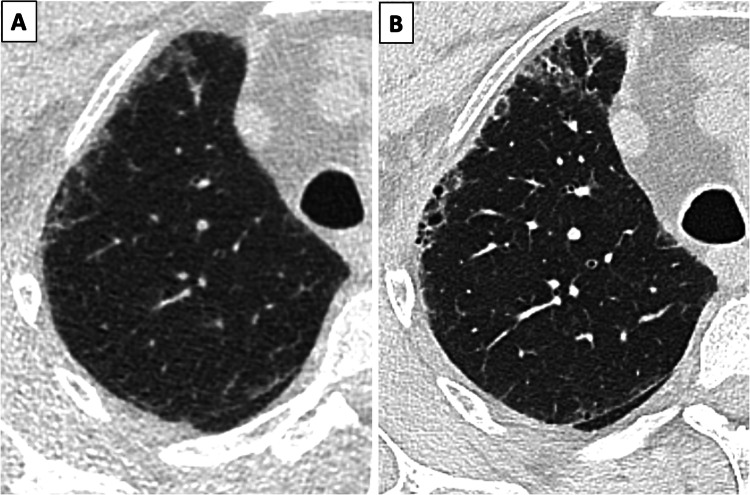

Pulmonary incidental findings are extremely common on LDCT-based LCS, being detected in up to 70% of subjects [49]. Among them, emphysema, and interstitial lung abnormalities (ILA) (Fig. 3) are the most frequently reported.

Fig. 3.

Example of ILA detected on baseline LCS low dose computed tomography (A), with evidence of progression toward over fibrosis at standard dose chest CT (B) performed after 36 months

ILA is defined as subclinical interstitial changes incidentally detected in subjects undergoing either abdominal or chest CT examination, without any clinical suspicion of underlying interstitial lung disease [57]. The estimated prevalence of ILA in LCS populations ranges between 4% and 20% [58]. The relationship between ILA and LC has been investigated in some LCS trials, and a higher prevalence of LC in screenees with ILA has been established [59], highlighting the importance of a risk-based LCS. Nevertheless, the clinical significance of ILA in the setting of LCS goes beyond the increased risk of LC. Indeed, some morphological subtypes of ILA, namely subpleural fibrotic, are associated with a higher risk of progression toward overt pulmonary fibrosis [60]. Clear guidelines on how ILA should be managed in the setting of LCS are still awaited. Quantification and characterization in non-subpleural, subpleural non-fibrotic and subpleural fibrotic are recommended, but whether the detection of ILA should prompt early referral for respiratory evaluation or managed with surveillance imaging is still to be assessed [52].